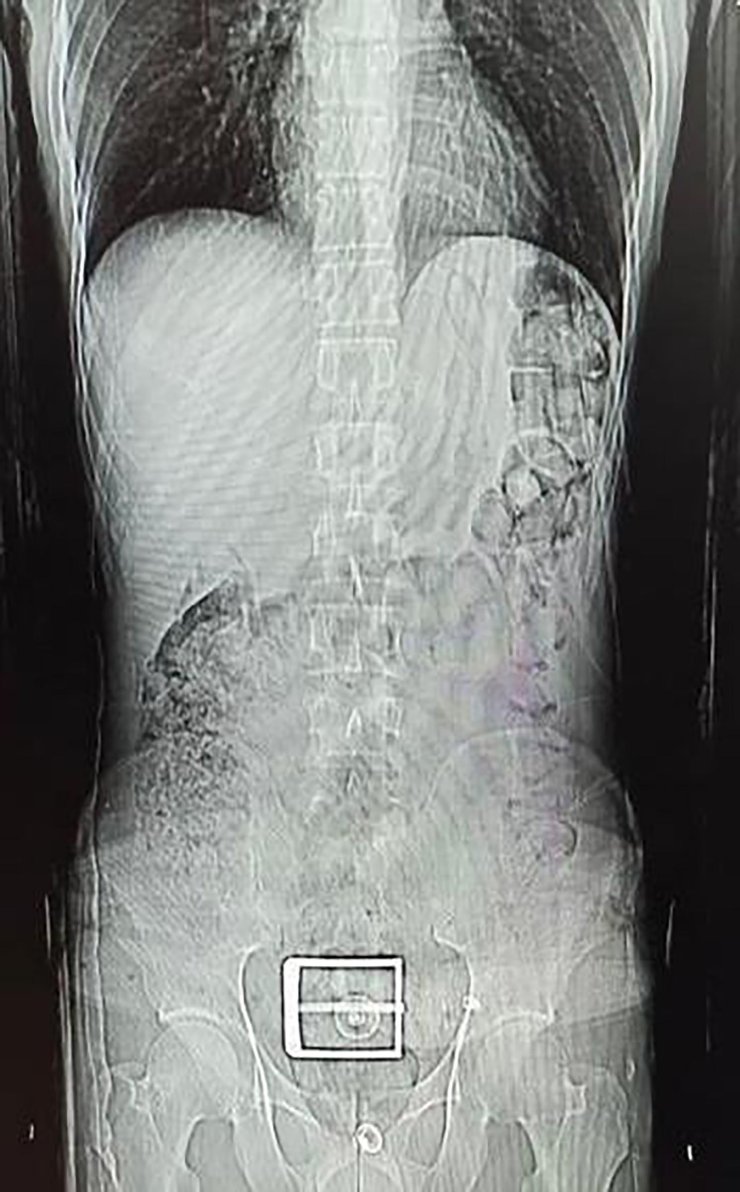

İl Emniyet Müdürlüğü Narkotik Suçlarla Mücadele Şubesi ekipleri, İran uyruklu F.S.'nin (30) durumundan şüphelenip, gözaltına aldı. Şüphelinin, götürüldüğü hastanede çekilen mide ve bağırsak röntgen çekimlerinde, çok sayıda yabancı cisim tespit edildi. Tıbbi müdahaleyle şüphelinin vücudundan 78 kapsül halinde 603,35 gram Afyon sakızı, 17 kapsül halinde 111,35 gram sentetik uyuşturucu çıkarıldı. Şüpheli, emniyetteki işlemlerinin ardından çıkarıldığı hakimlik tarafından tutuklandı.